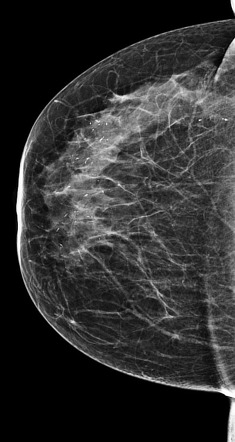

They appear as white spots or flecks on a mammogram but can't be felt during a breast exam. A new group has formed. For women treated for breast cancer in the past, calcifications may also be due.

There are a significant number. This is especially good for. Calcifications in a noncancerous growth called a fibroadenoma.